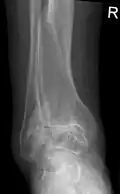

Diagnosis is made with reasonable certainty based on history and clinical examination.[52][53] X-rays may confirm the diagnosis. The typical changes seen on X-ray include: joint space narrowing, subchondral sclerosis (increased bone formation around the joint), subchondral cyst formation, and osteophytes.[54] Plain films may not correlate with the findings on physical examination or with the degree of pain.[55]

Arthrodesis (fusion) of the bones may be an option in some types of osteoarthritis. An example is ankle osteoarthritis, in which ankle fusion is considered to be the gold standard treatment in end-stage cases.[137]